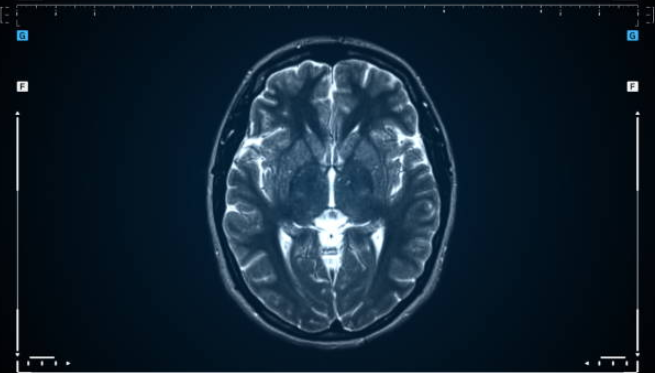

Alzheimer’s Pre-Diagnosis

an MRI-based diagnostic application designed to detect the early signs of Alzheimer’s long before visible symptoms emerge. Together with various neurologists with experience diagnosing and understanding Alzheimers, the app uses advanced pattern recognition to help physicians make diagnosis more accurate and faster for patients. This project seeks to revolutionize the way Alzheimers is identified and treated by allowing for the earlier intervention, bringing hope for better patient outcomes.